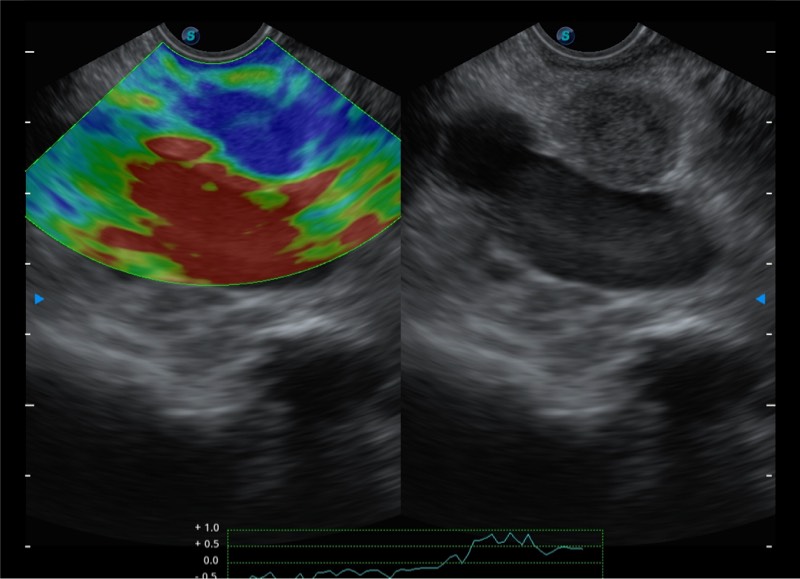

基于二十年的超声技术积累,银河优越会提供了最新一代的独立超声主机,在提供高质量图像的同时满足多学科使用。具备常见多普勒技术并提供弹性成像、声学造影等高端影像技术。新一代传感器具有更强的抗干扰能力并减少图像伪影。

4-12MHZ宽频输出